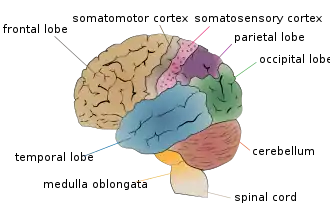

Primary somatosensory cortex: second image. | |

In neuroanatomy, the primary somatosensory cortex is located in the postcentral gyrus of the brain's parietal lobe, and is part of the somatosensory system. It was initially defined from surface stimulation studies of Wilder Penfield, and parallel surface potential studies of Bard, Woolsey, and Marshall. Although initially defined to be roughly the same as Brodmann areas 3, 1 and 2, more recent work by Kaas has suggested that for homogeny with other sensory fields only area 3 should be referred to as "primary somatosensory cortex", as it receives the bulk of the thalamocortical projections from the sensory input fields.[1]